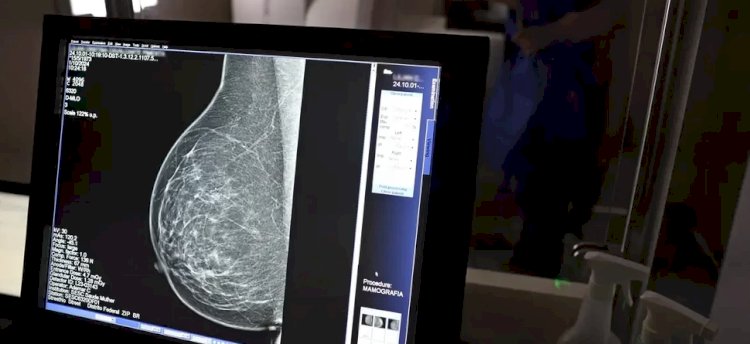

Paralelamente, o Ministério da Saúde ampliou a faixa etária para realização da mamografia no SUS , disponível agora para mulheres a partir de 40 anos, mesmo sem sintomas da doença. A medida visa fortalecer o diagnóstico precoce . Em 2024, mulheres com menos de 50 anos corresponderam a 30% das mamografias realizadas, ultrapassando 1 milhão de exames.